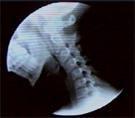

Videofluoroscopy